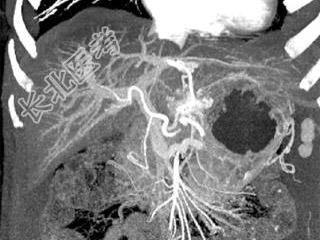

单项选择题根据所提供的图像,最可能的诊断是 ( )

A、肝癌

B、局灶性结节增生

C、血管瘤

D、胆管癌

E、以上都不是